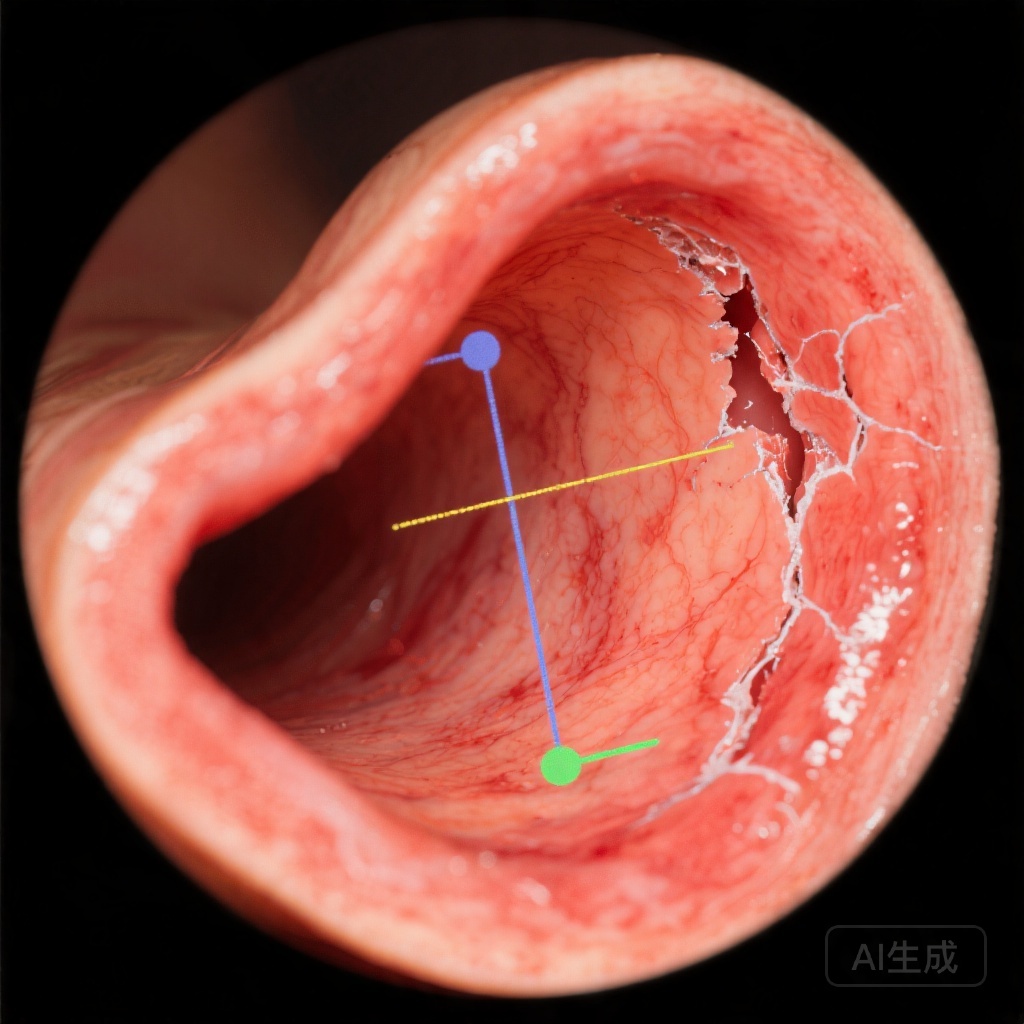

MIは、食道粘膜の電気抵抗を評価する内視鏡検査の一種で、その構造的健全性を反映します。インピーダンスが低下することは、慢性酸露出による粘膜損傷を示唆し、非侵襲性GERDでも観察されます。これは、pHモニタリングだけでは提供できない、逆流の負荷と症状発生の間の機序的な関連を示しています。

MI測定は、通常、専用カテーテルを使用して内視鏡検査中に実施されます。この手順は極めて低侵襲であり、一般的な診断フローに統合できます。主要な技術的側面には、測定部位の標準化と、最近の酸分泌抑制療法などの混在因子の回避が含まれます。

最近の研究では、GERD患者のMI値が対照群よりも一貫して低いことが示されており、症状の重症度との強い相関が見られます。特に、有効な医療または手術療法後、MIが改善することが示され、治療反応のモニタリングにおけるその有用性が示唆されています。手術集団からのデータは、術前MIがファンドプロリケーション後の結果を予測できる可能性があることを示しており、患者選択のための潜在的なツールとなっています。